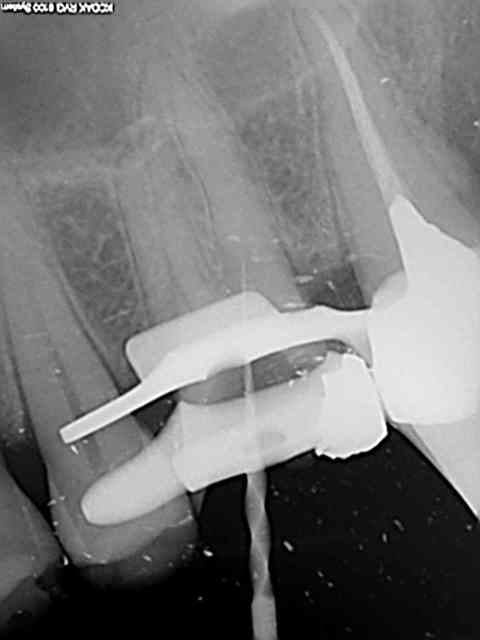

26, 60 mn endo molaire dont 30 pour trouver le canal DV (chambre calcifiée). J'ai failli jeter l'éponge mais le sx a fini par s'engager. Grosse frayeur toutefois avec le s1 sur endomaster car il a bipé d'ès son entrée dans le canal, mais c'était du à un excès d'irrigant. Ouf !

36, 30 mn endo molaire, vitesse de croisière retrouvée !))))